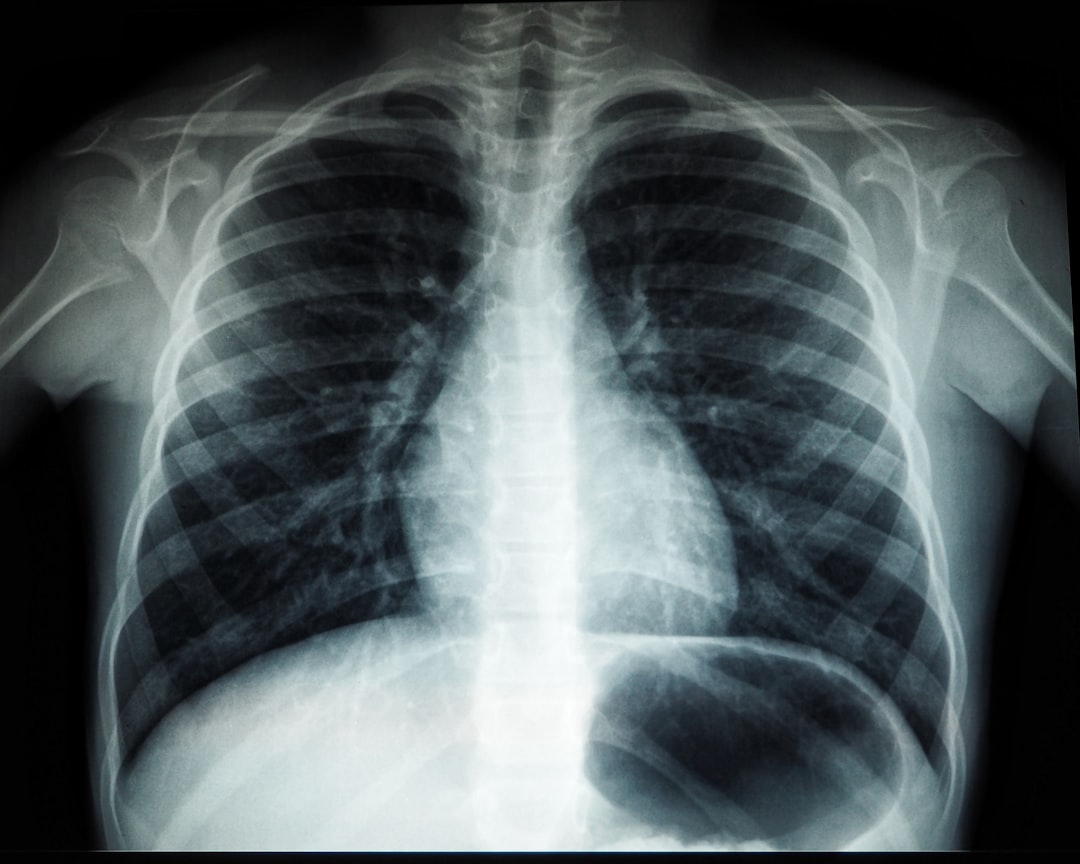

폐암초기증상 반드시 알아야 할 주요 징후

폐암의 초기 증상은 간과하기 쉬워 주의가 필요합니다. 잔기침, 손가락 변화 등 중요한 징후를 알아보며 건강을 지키는 방법을 살펴보겠습니다.